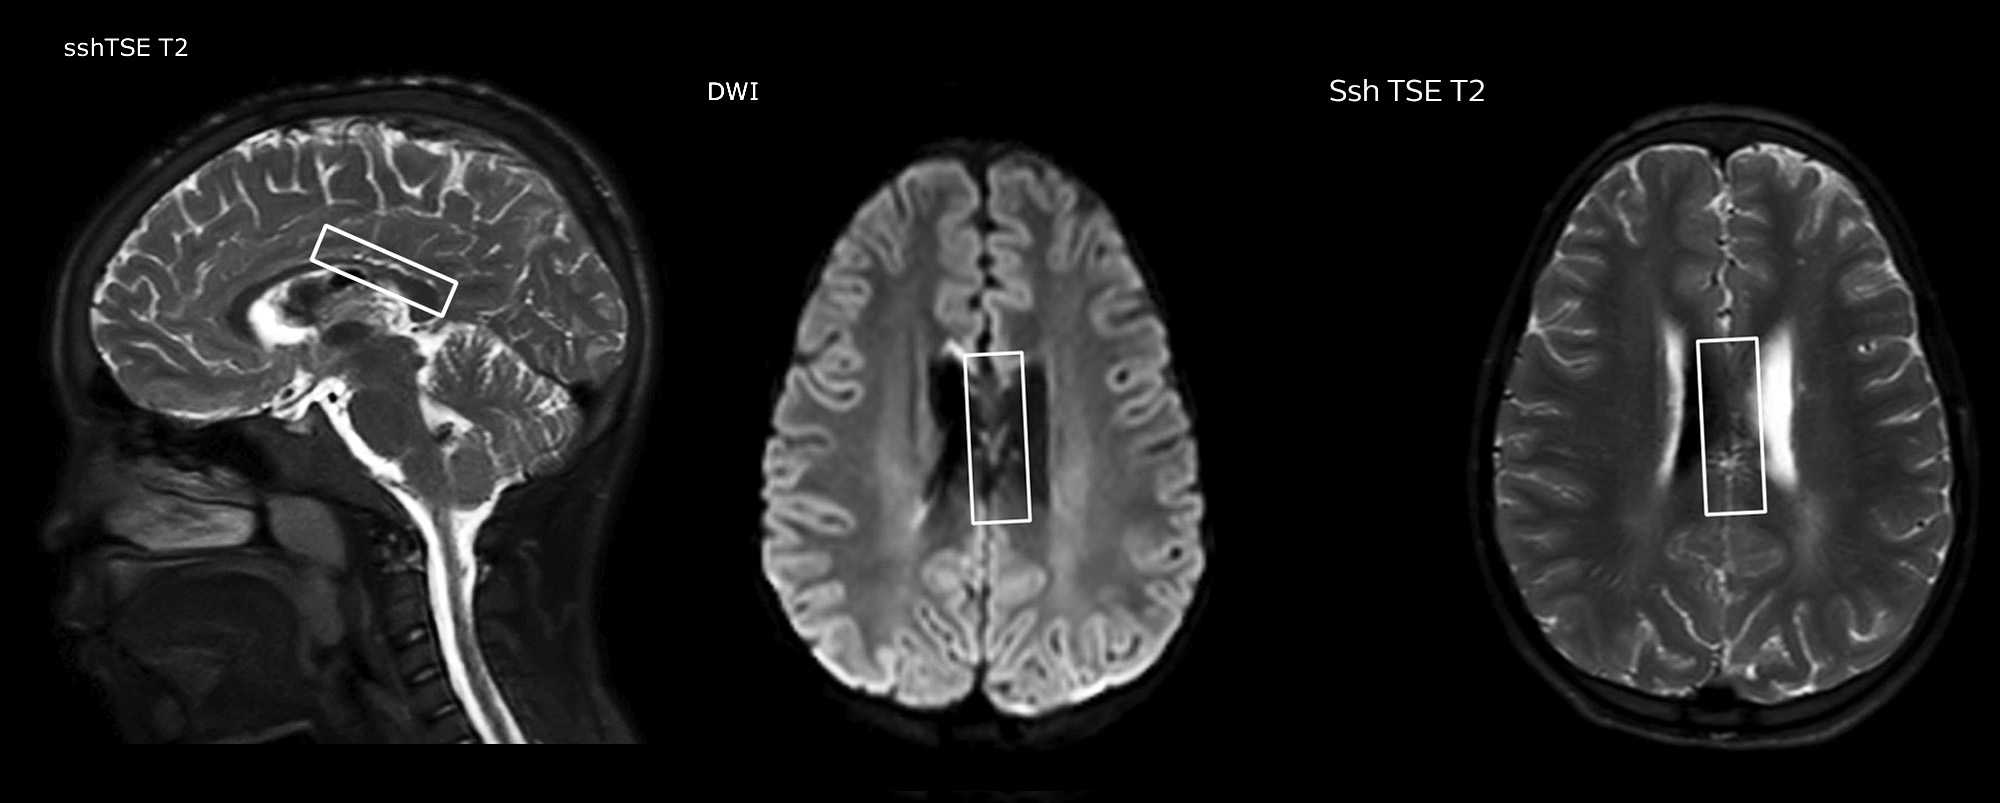

pCASL helps assess brain perfusion without contrast

Pseudo-continuous arterial spin labeling (pCASL) was developed for brain perfusion imaging without contrast agent. “This is very desirable in pediatric patients where the general trend is to limit the administration of contrast,” says Dr. Miller.

Dr. Miller uses pCASL for all patients who present with chronic and acute cerebrovascular abnormalities such as acute stroke, as well as patients who present with signs of acute inflammation in the brain, and occasionally in patients with tumors, to assess the perfusion status of their tumor.

“In combination with diffusion weighted imaging, it can help give a more extended assessment of the degree of perfusion abnormality in a patient who is suffering acute ischemia. We have a number of patients who have chronic arterial insufficiency due to prior arterial abnormalities or acquired arterial abnormalities such as sickle cell disease or neurofibromatosis. Sometimes the child’s first manifestation of disease progression is a reduction in brain perfusion before stroke symptoms manifest clinically or in diffusion weighted imaging. We use pCASL to help delineate the perfusion abnormality.”

“We built up confidence in pCASL by comparing it to contrast-based perfusion imaging. Once we had confidence that it was representing what the contrast perfusions were representing, we increased our diagnostic confidence by serial imaging in either the acute stage or the long term stages in a number of patients with arterial abnormalities.

To other new users I would recommend to also start to interpret the pCASL images in comparison with other standard imaging – T2 and FLAIR and DWI – until the user gains confidence in interpreting these images by themselves.”